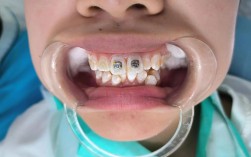

选择经验丰富的正畸医生

正畸治疗需综合考虑牙齿、骨骼、肌肉、软组织等多因素,经验丰富的医生能通过精准测量(如头影测量、数字化口扫)预测拔牙后的效果,避免“过度拔牙”,对于 borderline case(临界病例),医生可能通过“不拔牙试戴”观察牙齿移动情况,再决定是否拔牙。

充分的术前沟通与方案设计

患者需主动向医生说明诉求(如希望改善的面部细节、对拔牙的顾虑),医生则需详细解释拔牙的必要性、拔牙数量、预期效果及替代方案,对于青少年患者,可通过“生长改良治疗”(如功能矫治器)利用颌骨生长潜力减少拔牙需求;对于成年人,若担心拔牙,可考虑种植体支抗(植入微型种植钉辅助牙齿移动),实现“不拔牙矫治”。

治疗过程中的动态调整

正畸治疗周期通常为1.5-3年,医生需定期复诊(每4-6周),观察牙齿移动情况、咬合变化及患者反馈,若发现拔牙后效果不理想(如内收不足或过度),可及时调整矫治力,避免偏差扩大。